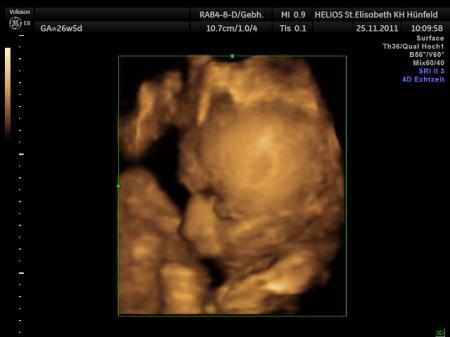

habe heute morgen untersuchung und ctg gehabt und alles bestens der kleine ist jetzt bei 32+5 ssw ca 28 cm und 1800 gramm schwer alles zeitgerecht entwickelt gebärmutterhals gut hat sich auch nichts verändert. so und gleich gehts zur kreissalbesichtigung mit meinen mann freu mich schon lg nadine

Bild zu